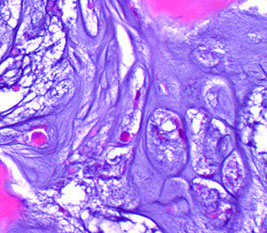

Hyperparathyroidism - Brown tumors. Right image shows zone of bone resorption in center c defect filled c fibroblastic tisuue, and around the periphery is osteoid-producing area that looks like fibrous dysplasia. Image on left is close of area replacing fibroblastic tissue c lots of osteoclast-like GCs, that may lead to misdiagnosis of giant cell tumor (except GC tumors usually lack fibrogenic stroma)

Brown Tumor

Bone loss causes microfractures and hemorrhage causing macrophage influx and reparative fibrous tissue

Brown from vascularity, hemorrhage and hemosiderin deposition

"Brown tumors" of bone are caused by hemorrhage and hyperparathyroidism

- may also be caused by pseudohyperparathyroidism, but is usually due to parathyroid adenoma, hyperplasia, or rarely carcinoma or chronic renal failure

Osteitis fibrosa cystica

- aka von Recklinghausen's disease of bone

Imaging: erosion of tufts of terminal phalanges and subperiosteal cortical resorption, esp on the radial side of the middle phalanges

Micro: Osteoclasts line cystic spaces (tunneling), which also have a very fibrous stroma, inc formation of woven bone, and peritrabecular fibrosis, MNGCs

Labs: Inc Ca and ALP, low PO4